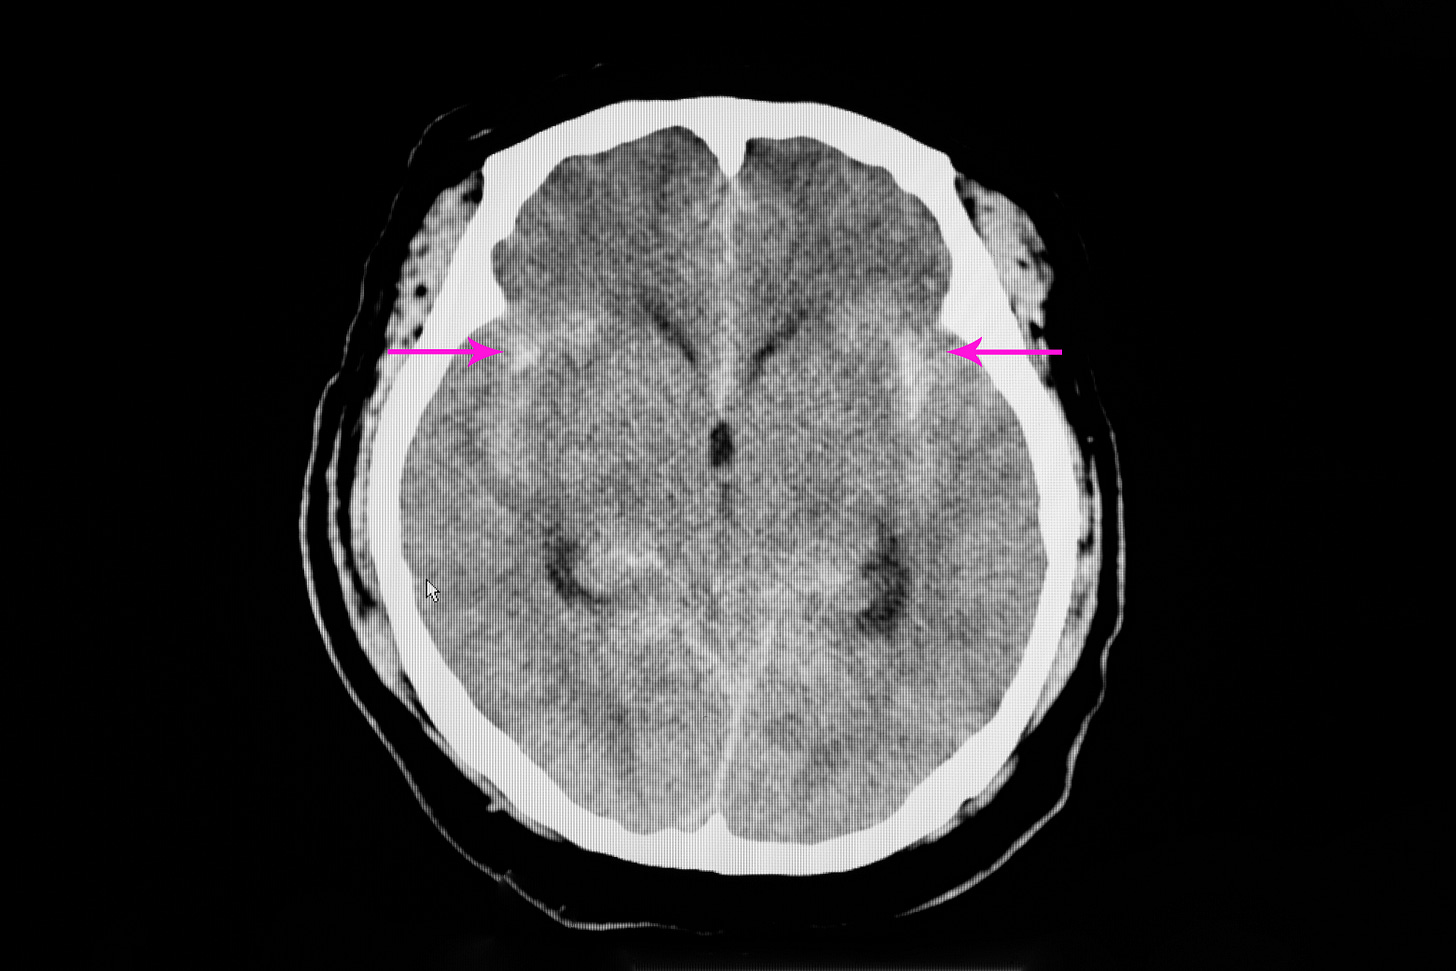

Brain-injured patients, including those with traumatic brain injury (TBI) and hemorrhagic strokes, were not well-represented in randomized trials studying transfusion thresholds in critical illness. Anemia—or transfusion—might be more harmful to injured brains than non-injured ones, for various reasons.

Three randomized trials published in 2024 provide some evidence to inform transfusion decisions in brain-injured patients, although the trials suffer from possible underpowering and (in one) aggregation of unalike patients.